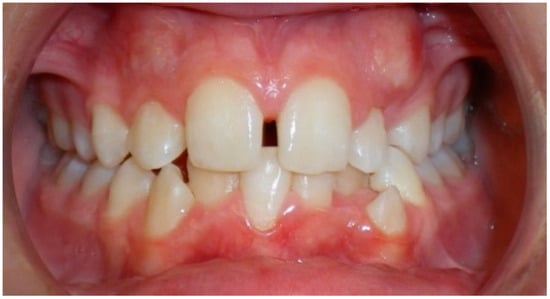

- Evaluation of impacted teeth, a common indication of CBCT in orthodontics. The advantages of CBCT include assessment of the tooth location and position, the stage of development, and status of adjacent teeth. CBCT is justified in these cases, because CBCT has the capability of evaluating the impacted teeth and adjacent structures more accurately than 2D conventional imaging. The benefit–risk ratio is favorable, especially if the CBCT volume is collimated to the impacted tooth. Figure 1, Figure 2, Figure 3 and Figure 4 show an example of impacted maxillary canines, and their proximity to the maxillary lateral incisors. Figure 1 shows an intraoral photograph. The benefit of CBCT acquisition in this case includes the ability to visualize the canines and the lateral incisors in three dimensions, which can be visualized in Figure 2 and Figure 3. In this case, the maxillary right lateral incisor exhibited external root resorption, a finding that would be difficult to see on a conventional 2D panoramic radiograph. Figure 4 shows a Maximum Intensity Projection of a panoramic view derived from the CBCT volume. This unique view is free of magnification, distortion, ghost images, and overlaps frequently seen in conventional 2D panoramic radiography.